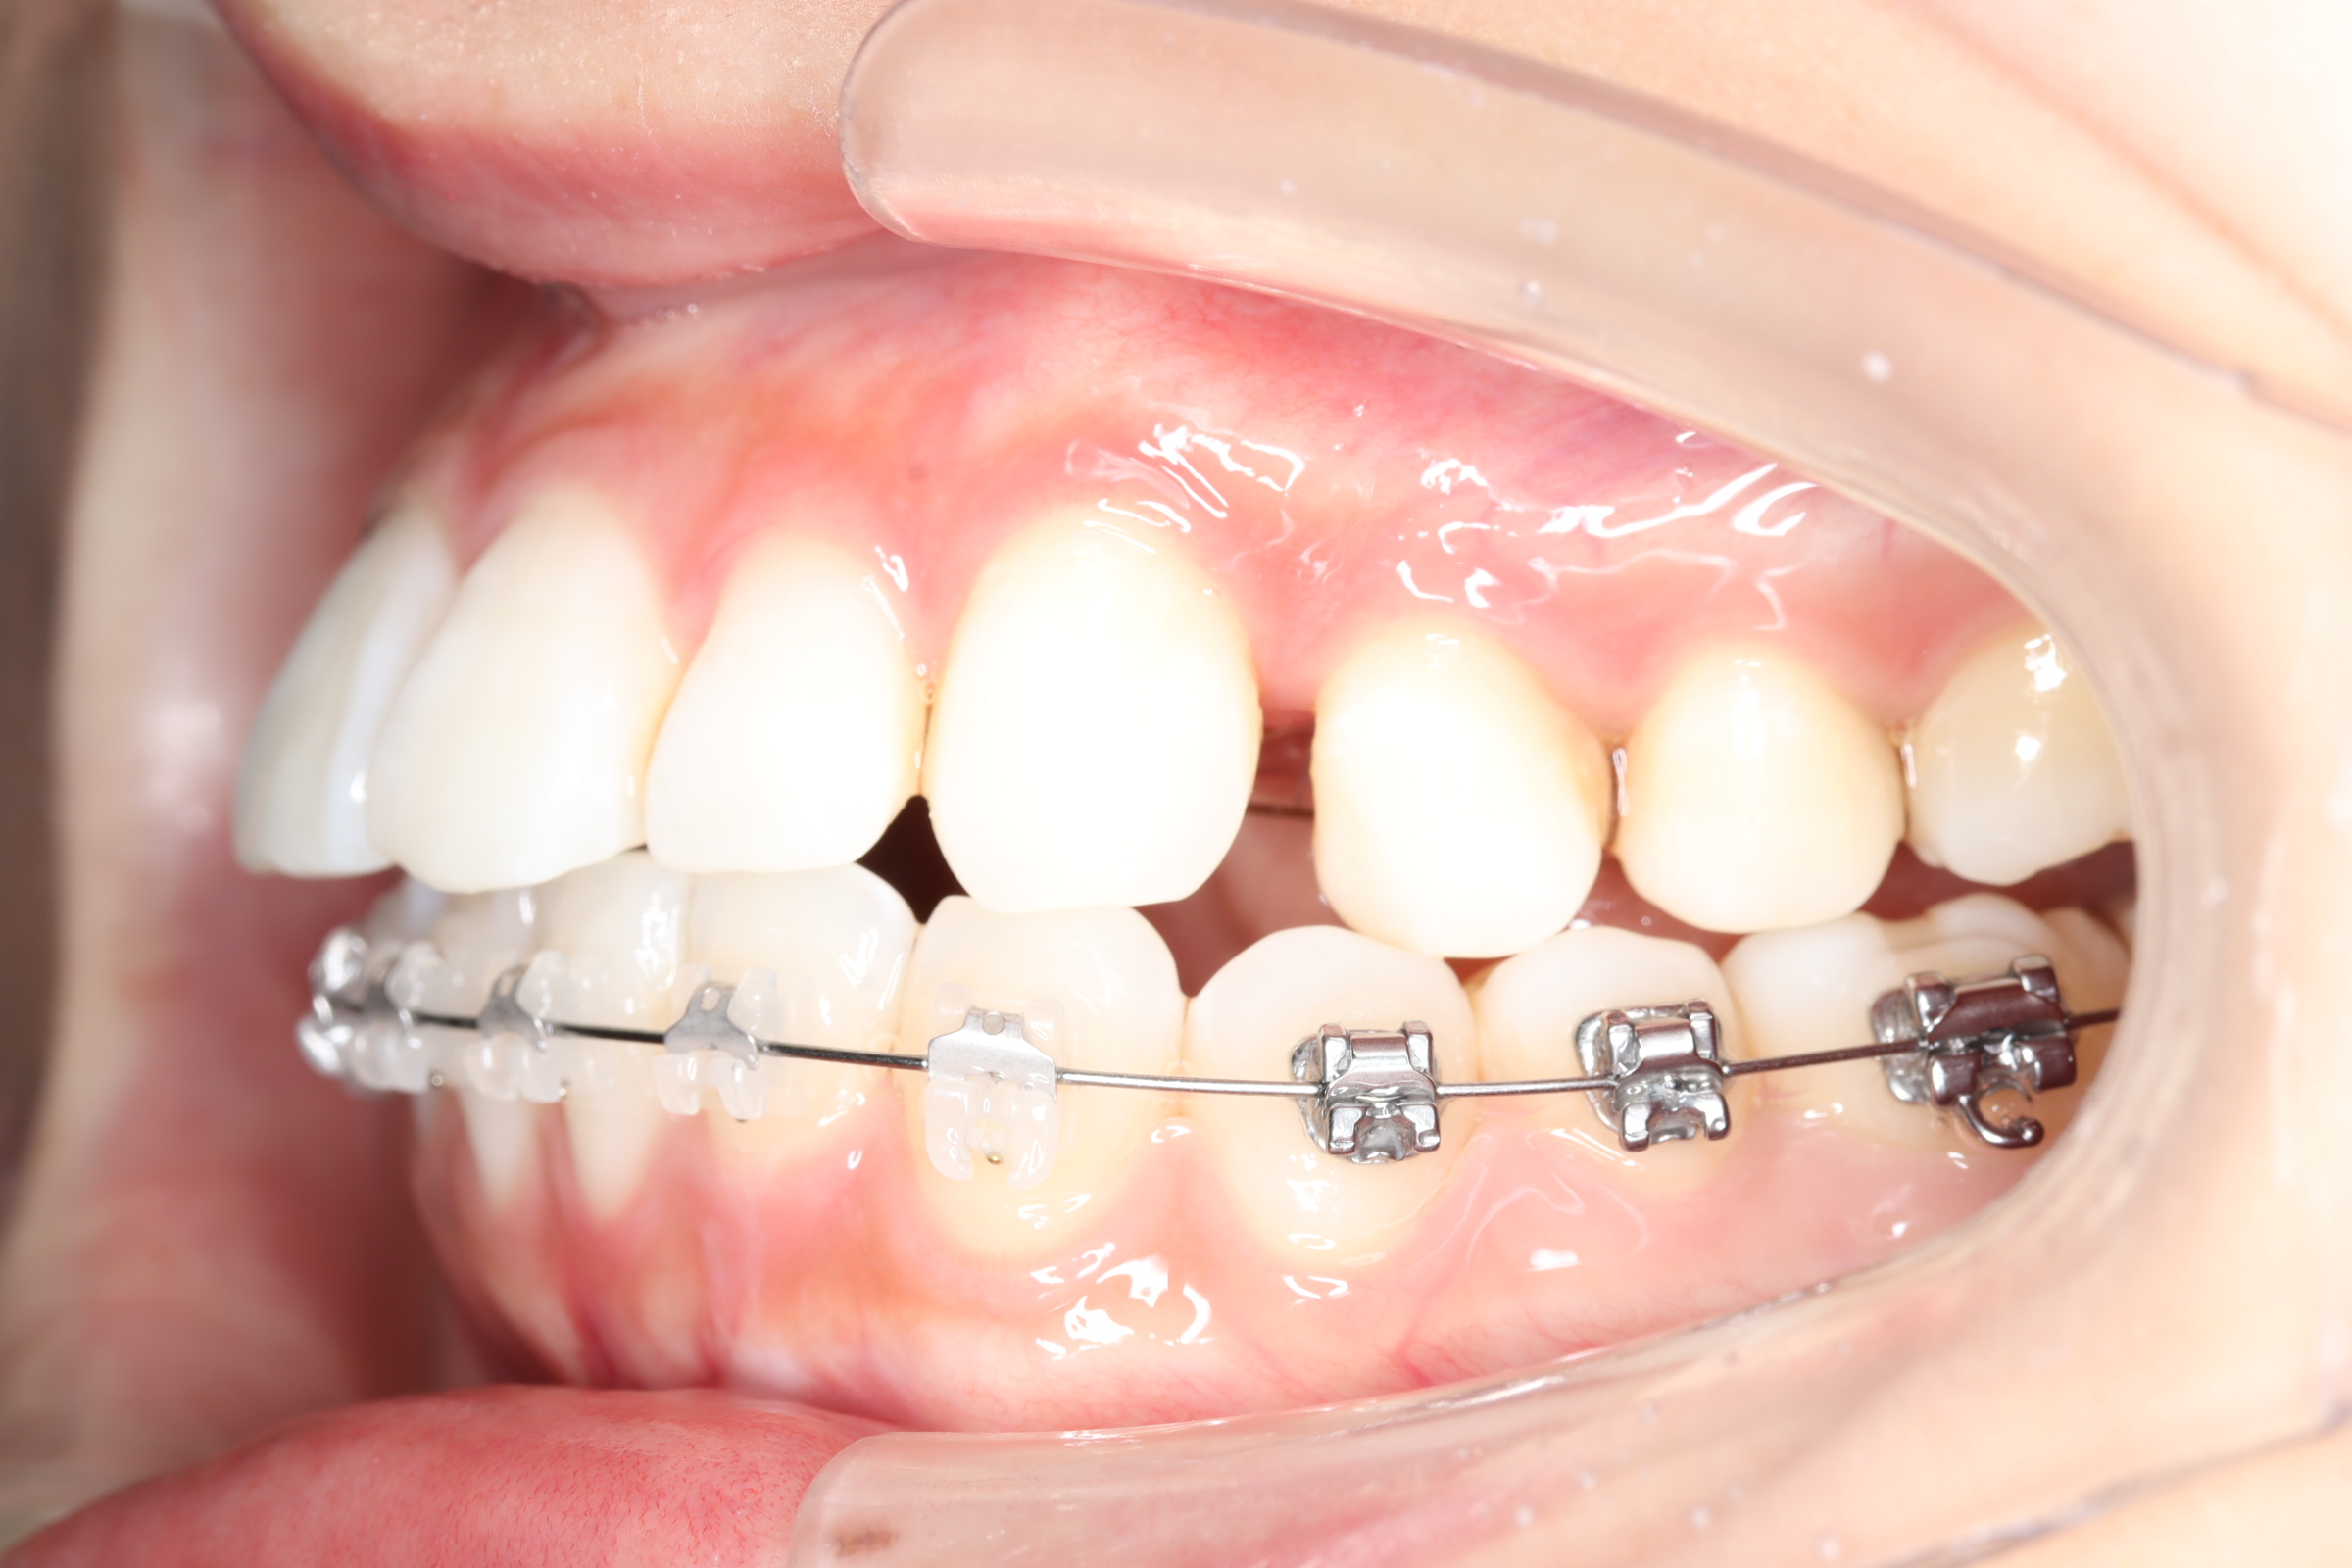

治療中

![]() | ![]() | ![]() |

| 使用矯正装置 | 上顎:セルフライゲーションリンガルブラケット 下顎:セルフライゲーションブラケット(セラミッククリッピー) 歯科矯正用アンカースクリュー |